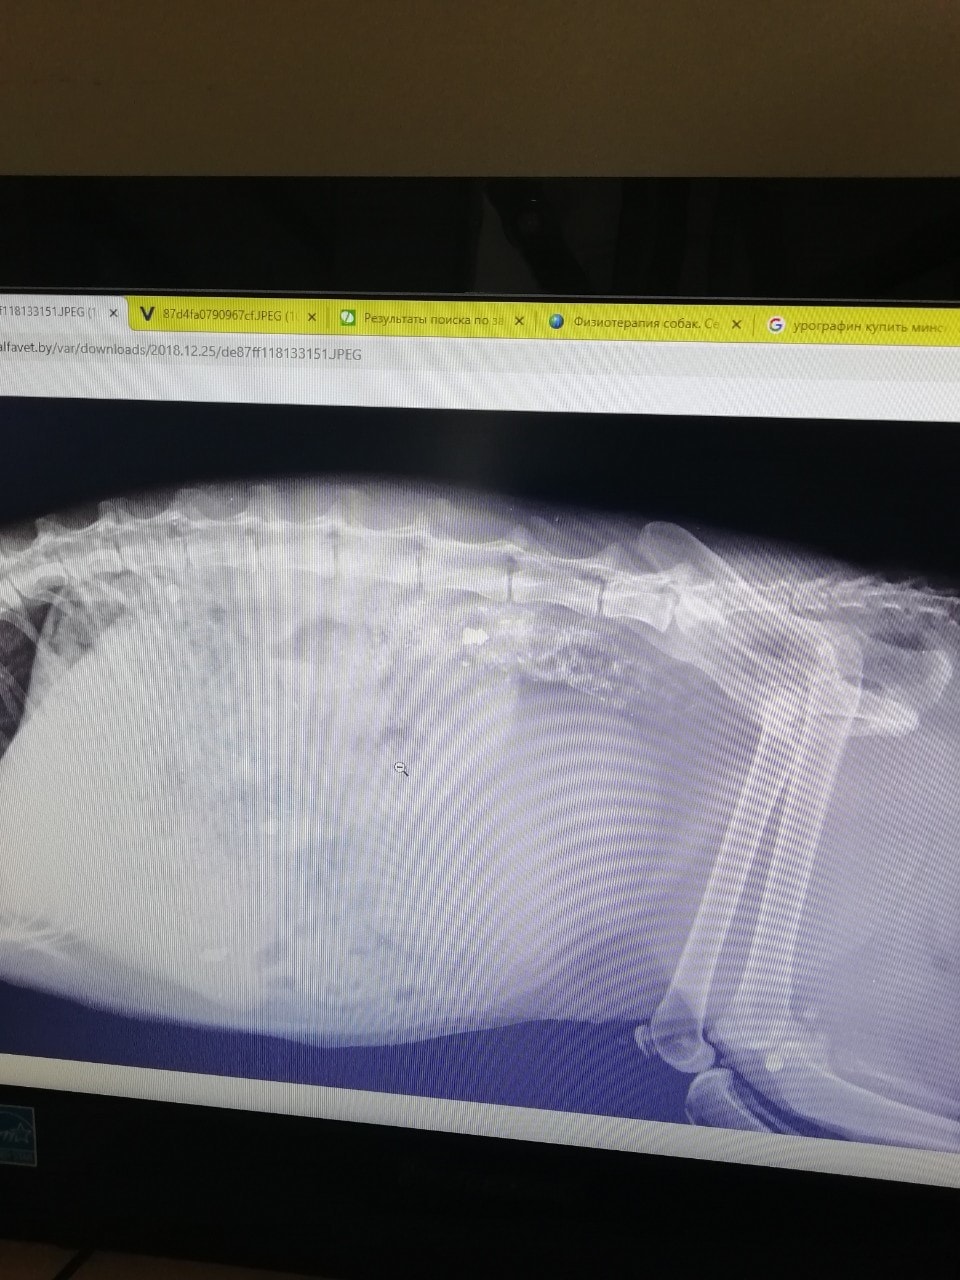

Сделали рентген и охнули.

Операцию делать не стали — кот не в том состоянии, чтобы ее просто пережить. Поставили катетер, чтобы он мог хотя бы облегчиться.